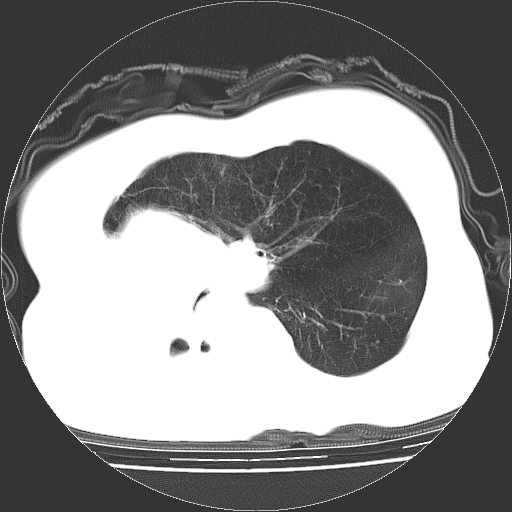

标题: CT23991:女,72岁,咳嗽、憋气一周。 [打印本页]

女,72岁,咳嗽、憋气一周,十年前曾患肺结核及胸膜结核。

右侧毁损肺,右侧纵隔疝,左肺代偿!

右侧肺硬变,左肺代偿气肿。

1.右侧损毁肺伴胸膜钙化,2.左肺小结节灶,良性可能大,注意复查。3.肝脏左叶囊肿。4.先天性一侧肺不发育待出外(右侧胸廓无明显塌陷)。对比原片应该非常有帮助。

右侧肺毁损,左肺代偿性肺气肿,纵隔疝。